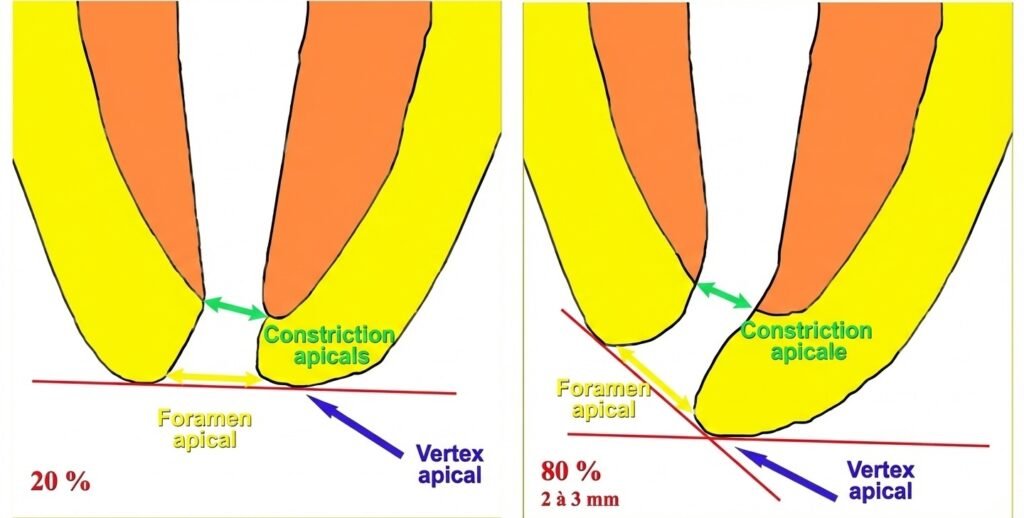

Les Structures Apicales : Repères Indispensables

Plusieurs structures anatomiques guident votre travail dans la zone apicale :

- Apex anatomique : le sommet de la racine, le point le plus visible

- Apex radiographique : l’image projetée sur la radiographie

- Constriction apicale : la zone la plus rétrécie, point de référence crucial pour la longueur de travail

- Foramen apical : la sortie principale vers le parodonte

- Jonction cémento-dentinaire (JCD) : limite entre dentine et cément